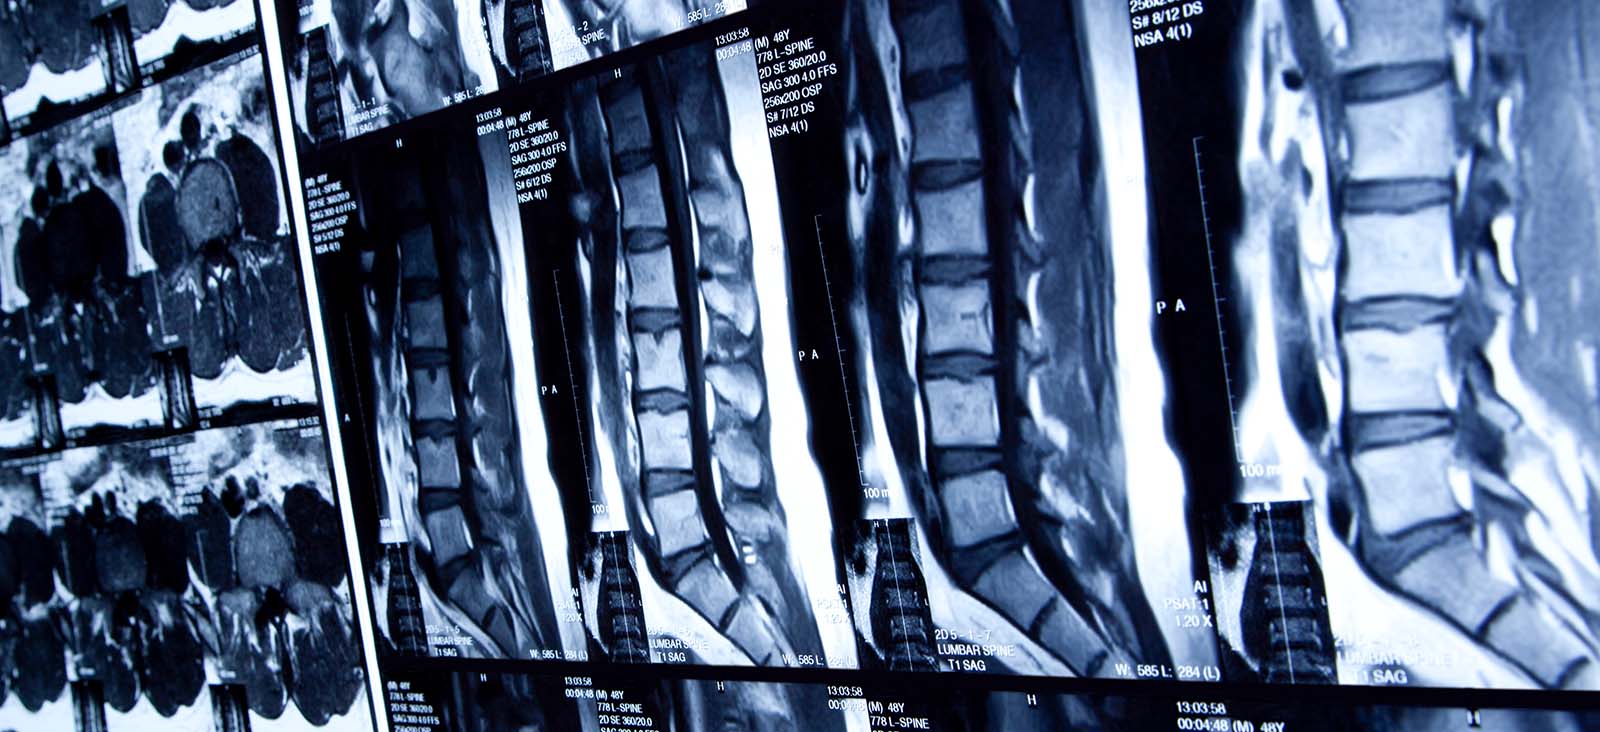

MRI services take place in the Mary Nell and Ralph B. Rogers Magnetic Resonance Imaging Center, located onsite.